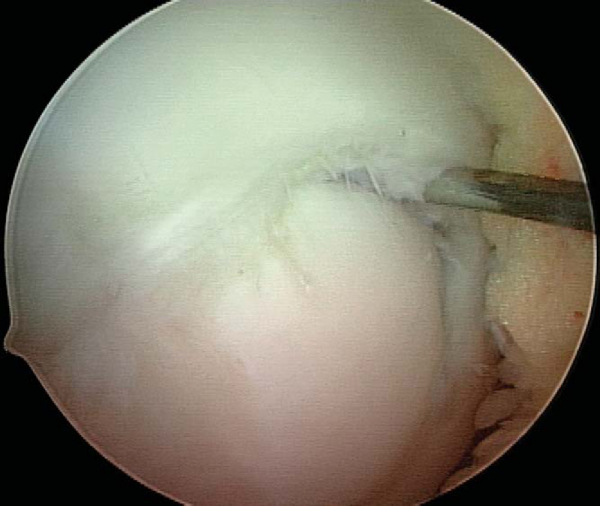

2. Identification and Assessment of Lesion Stability

With use of the elbow of a standard arthroscopic probe, the boundaries and stability of the lesion are assessed. In many cases, the borders of the lesion are obvious, with fissuring, fibrillation, and even gross gapping in the articular surface (

Fig. 53-3

). However, definition of the lesion can be more subtle in some cases. Nevertheless, even without obvious visual clues, a distinct transition from firm to soft or the ballottement of a segment of articular cartilage can typically be appreciated as one moves the elbow of the probe from normal cartilage to that overlying an osteochondritis dissecans lesion. The tactile feedback received is that of the elbow of the probe falling into a small crevasse as the lesion boundary is crossed (

Fig. 53-4

). In the rare case that the lesion cannot be identified through visualization and tactile feedback, intraoperative fluoroscopy can confirm the lesion’s location.

Figure 53-3   |